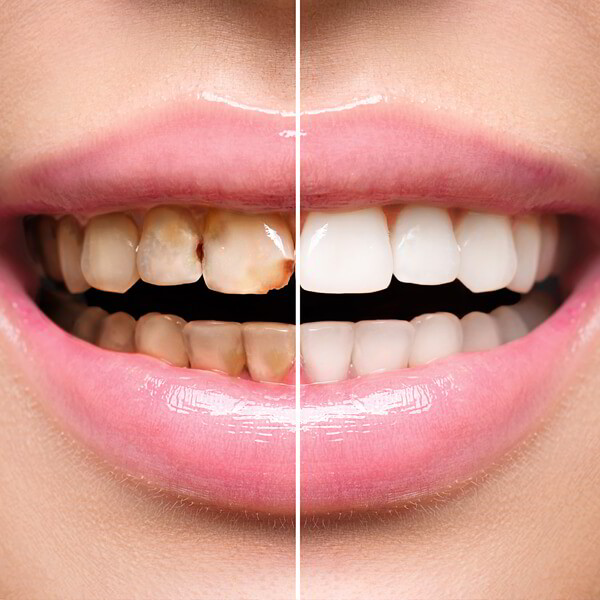

Tooth filling is a very popular dental treatment, when the decayed and damaged tissues replaced by dental materials. Filling helps to prevent the development…